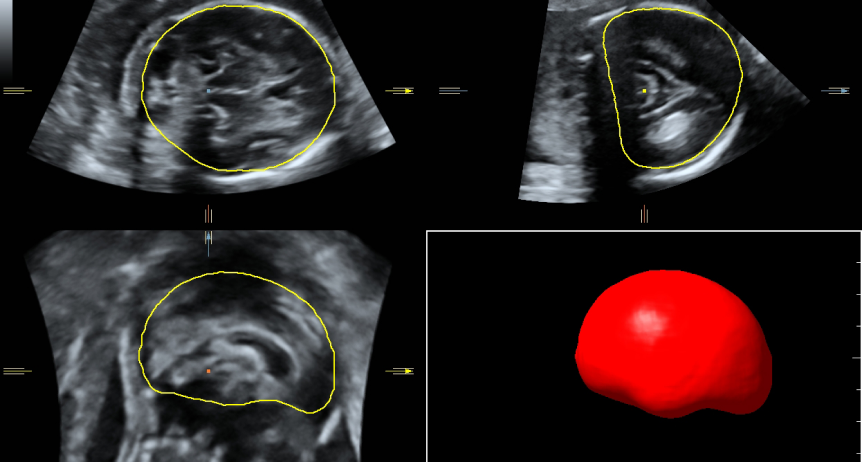

SMART CNS

SMART ICV FETAL